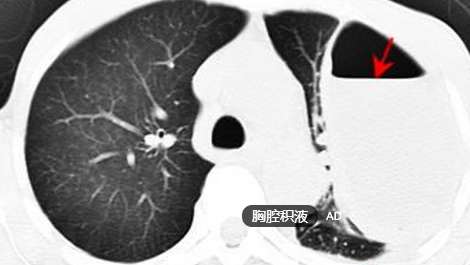

吴女士的胸部疼痛就这样持续了三天,一直未见好转,且还伴有发热。不料一日清晨,正在医院照顾老伴的她,突然开始大口吐血,继而休克。医护人员立即将吴女士送往了急诊室,经过两小时的紧急手术,可算脱离了危险。医生在替吴女士做检查时发现,她的胸腔里积满了脓液,肺部被挤压得只有正常大小的1/2,脓液抽出来足足有2000毫升。“刹车只是造成胸痛的诱因,元凶其实是大量的胸腔积液所致”医生告知。

后经协商,该院医生在B超监测下,穿刺孕妇肚皮、胎膜和胎儿胸腔,放置了一条进口的“猪尾巴”,顺利排出了胎儿的胸腔积液。据医生介绍,胎儿胸腔积液在临床上并不少见,其发病率在万分之一到五万分之一之间。胸腔积液会令胎儿肺部发育受限、食道受压、羊水过多、心脏和血管受压引发的水肿,进而导致早产或胎死宫内,因此及早发现和治疗很重要。

专家提醒:胸腔积液起初并不会有比较明显的症状,因此很多朋友都会对其忽视。而一旦胸腔积液形成恶性,就会带来比较严重的危害。在此提醒大家,若是日常出现胸痛、发热的症状,且呼吸困难,还需警惕患上胸腔积液。同时,孕妈妈们还需做好定期体检,一旦发现胎儿异常,要及早采取治疗措施,以免遭受其害。